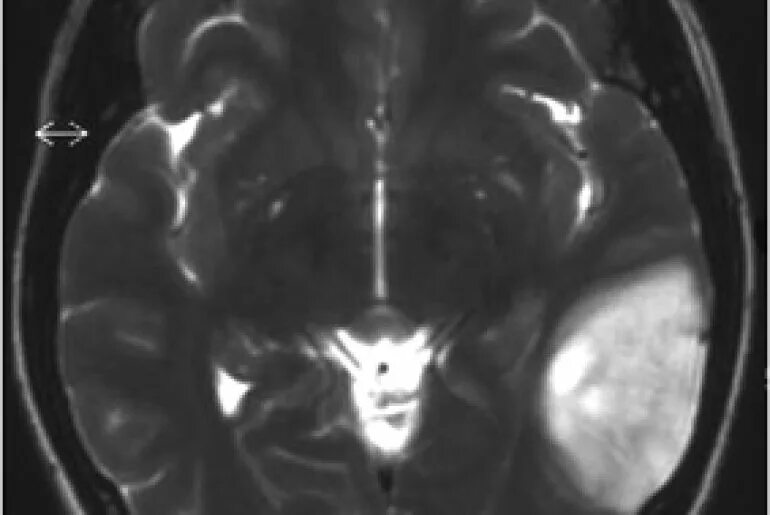

Рак неоперабельный 4 стадия